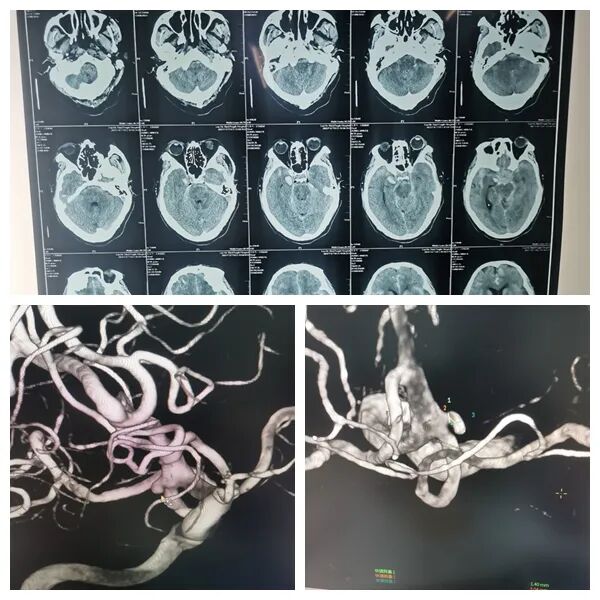

该患者男性,76岁,以“突发头痛伴恶心呕吐3小时”为主诉入院,急诊完善头颅CT提示蛛网膜下腔出血,考虑颅内动脉瘤可能性大。经积极术前准备,稳定血压,预防脑血管痉挛等药物应用,急诊局麻下行脑血管造影提示:左侧颈内动脉后交通段动脉瘤。

为预防动脉瘤再次破裂、降低致死致残率,神经外科与家属沟通后,急诊全麻下行动脉瘤弹簧圈单纯栓塞术,术后即刻造影提示动脉瘤致密填塞,载瘤动脉血流正常。术后患者顺利苏醒,言清语利,四肢肌力肌张力正常。后经治疗,患者头痛症状基本消失,四肢活动无受限,言清语利,四肢肌力肌张力正常,目前已顺利出院。